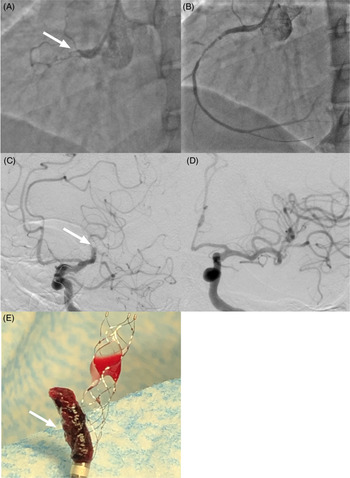

The patient is a 59-year-old male who was previously well until he developed progressive dyspnea over 3 days. He was diagnosed with non-ST elevation myocardial infarction (NSTEMI). He did not have hypertension or diabetes, but had a preexisting diagnosis of Ebstein’s anomaly. He underwent PCI 6 days after symptom onset. The left circumflex artery with a 70% mid-vessel stenosis was stented. The right coronary artery (RCA) was totally occluded proximally by thrombus. After a second balloon dilation (2.0 × 20 mm Sprinter Legend Balloon, Medtronic), the thrombus disappeared (see Figure 1A–B). After stent placement in the RCA, the patient became agitated and subsequently confused. The symptoms were attributed to periprocedural sedation. In recovery, he became dysarthric; consequently, a code stroke was called. He had an NIHSS of 7 (aphasia and dysarthria). He was unable to follow commands and spoke gibberish. The initial plain cranial CT showed an Alberta Stroke Program Early CT Score (ASPECTS) of 6 (left insula, M2, M3, and M6) and an occlusion at the left M1–M2 junction. He underwent successful (TICI 3) thrombectomy with a combined stent retriever (4 × 40 mm Solitaire, Medtronic) and aspiration (ACE 68, Penumbra) approach (see Figure 1C–F). Three months later, he only had moderate expressive aphasia.

Figure 1: Cardioembolic right coronary artery (RCA) clot going to the left middle cerebral artery. (A) Angiography demonstrating a thrombus (white arrow) in the proximal portion of the RCA. (B) After balloon inflation, the thrombus has disappeared. (C) Cerebral catheter angiography demonstrates a thrombus (white arrow) in the M1–M2 junction of the left middle cerebral artery. (D) TICI 3 reperfusion of the left middle cerebral artery after endovascular thrombectomy. (E) Mature clot (white arrow) in the stent retriever and the aspiration catheter.